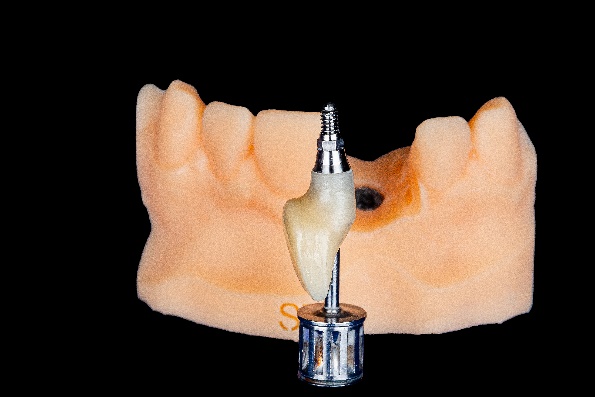

The surgical guide, made from transparent resin, was printed using Shining 3D’s AccuFab-D1s printer. After positioning the guide, the bone grafting area was precisely identified with its assistance. Implant socket drilling was carried out step-by-step under the guide’s direction, and the implant was successfully placed with excellent primary stability. (Fig 9, Fig 10)

The bone material was implanted and covered with a non-resorbable titanium-reinforced Polytetrafluoroethylene (PTFE) membrane, which served as a barrier to prevent cell occlusion. The edges of the membrane were secured with a titanium nail(Fig 12,Fig 13)